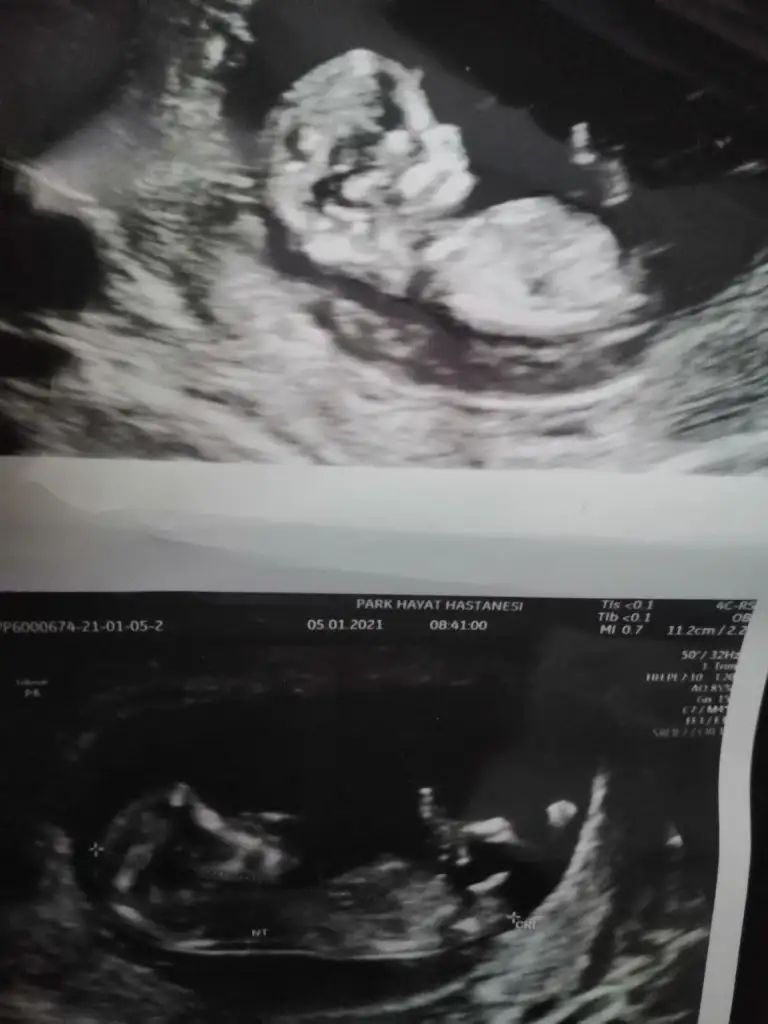

Çok teşekkür ederim.. burada 10+4.. başka hiç bu şekilde nubu görünen yok malesefBu kaç haftalik erkek görünüyor en iyi 11 12 13 haftalar olmalı

Maşallah bacım vallahi nasıl bukadar anlıyorsun yaEminde olamadımerkek gibi bu gördüğüm nub iseEki Görüntüle 2752680

Erkek görünüyorMerhabalarIkra meyra

Erkek görünüyor kesede karindansa kız vajinal ise erkek diğer USG kaç haftalık en iyi 11 12 13 haftalar olmalıMerhaba ikra meyra arkadaşımın bebişine de bakarmısın kese ve nubunaEki Görüntüle 2753467 Eki Görüntüle 2753468 Eki Görüntüle 2753470

Erkek gibi sanki eminde olamadımUsg net değil şimdi net bı bakar mısın Eki Görüntüle 2753582 Eki Görüntüle 2753583 Eki Görüntüle 2753585

Kese karından usg 12 haftalıkErkek görünüyor kesede karindansa kız vajinal ise erkek diğer USG kaç haftalık en iyi 11 12 13 haftalar olmalı